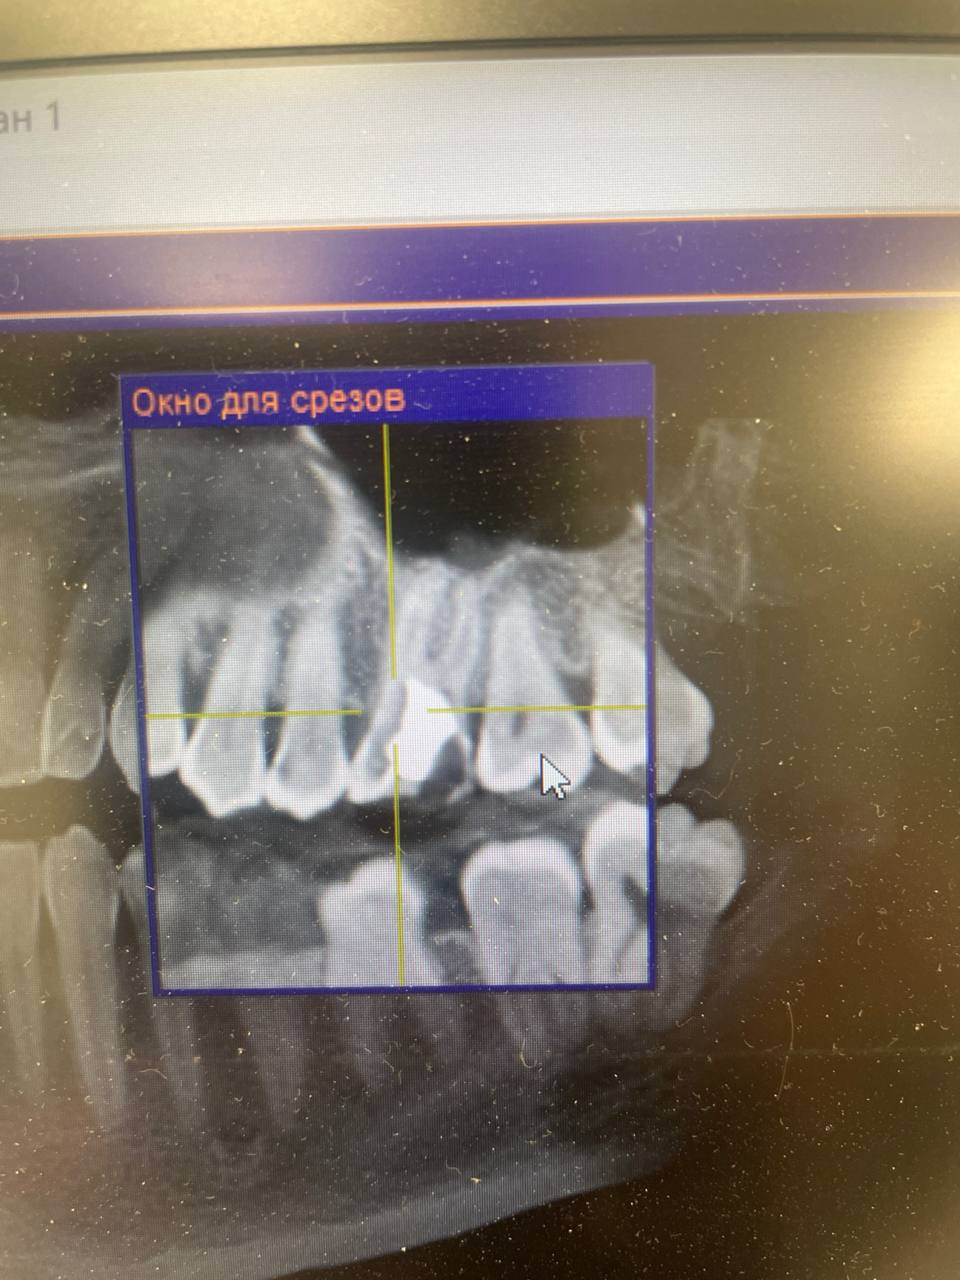

960x1280

>>1657604

Вот даже кусок старого рентгена остался трёхлетней давности